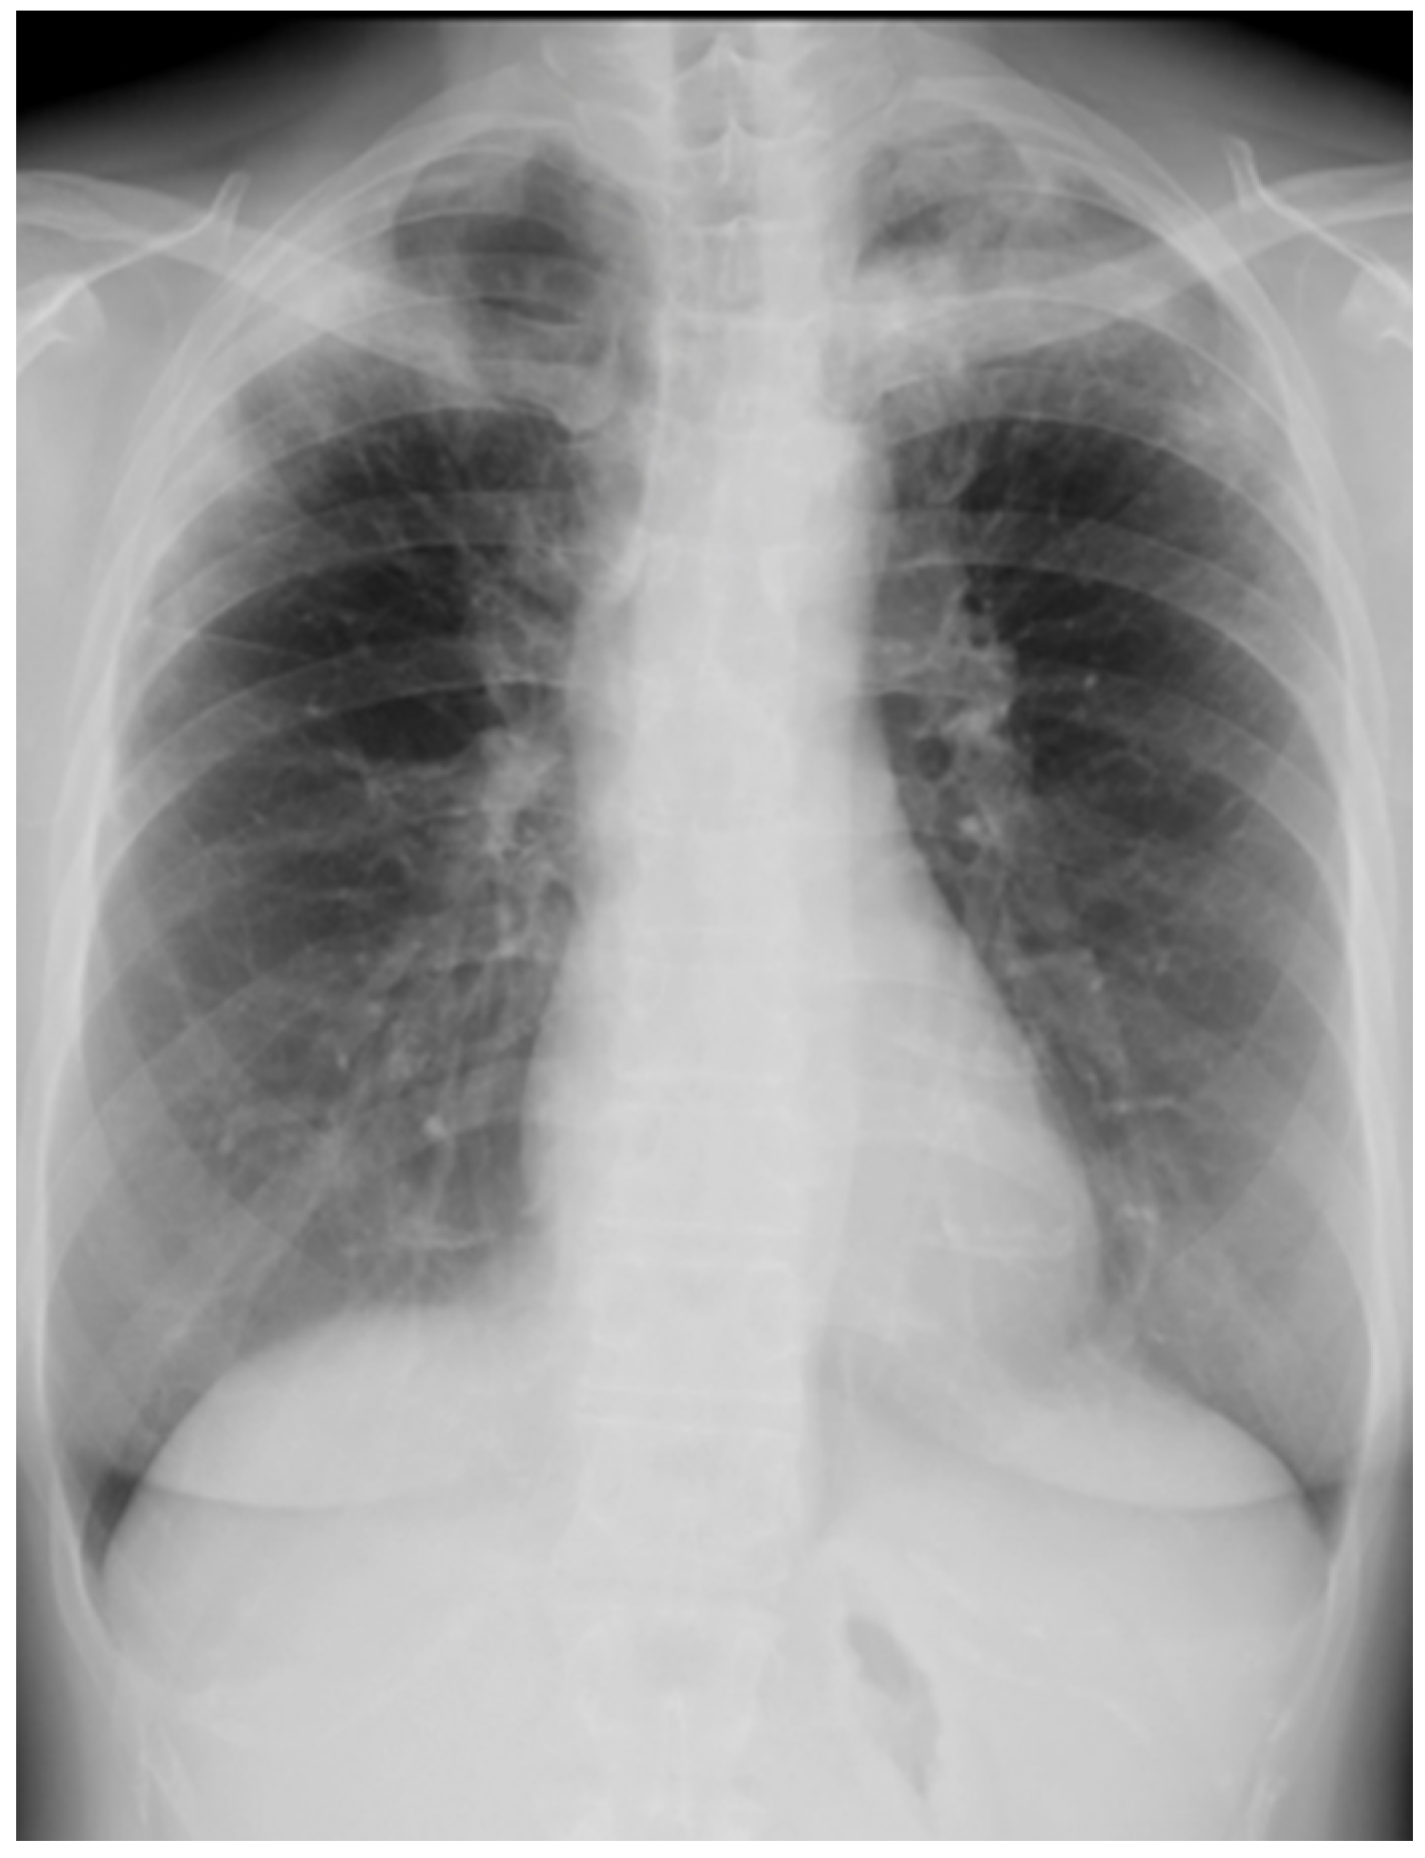

Her chest X-ray on admission showed consolidation in the bilateral peripheral-based upper lung fields and a typical radiographic pattern, i.e., “photographic negative of pulmonary edema” [3]. (Figure 1) Chest computed tomography (CT) revealed extensive ground-glass opacities in the left lung with contractile changes. Non-regional consolidation was scattered throughout the peripheral upper and middle lobes of the right lung (Figure 2).

Figure 1. Chest X-ray of 55-year-old woman upon admission with fever and dyspnea. It showed bilateral consolidation in her upper lung fields.